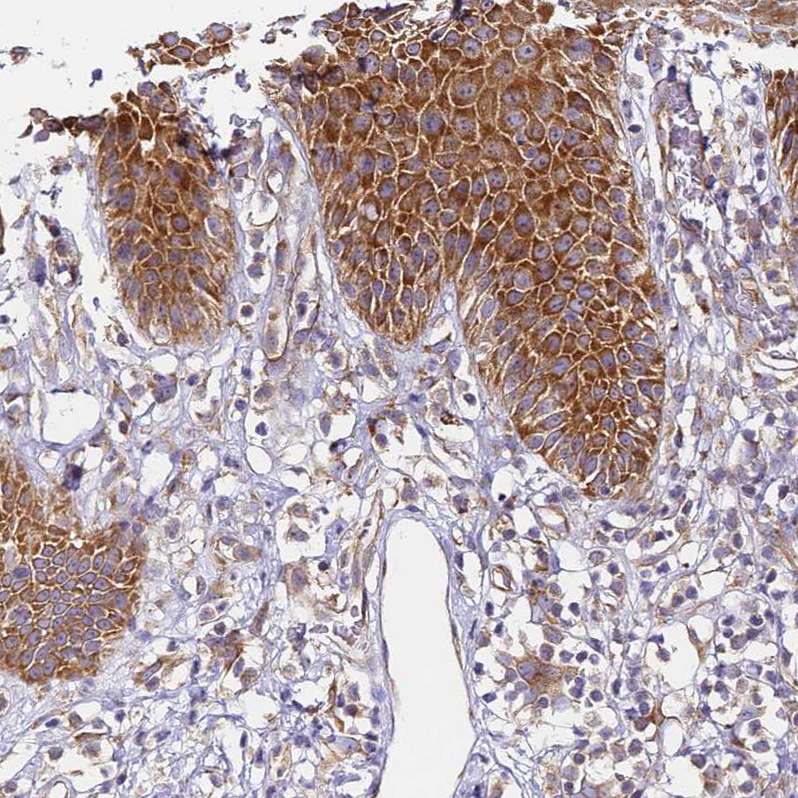

Immunohistochemical staining of human fallopian tube shows strong cytoplasmic positivity in glandular cells.